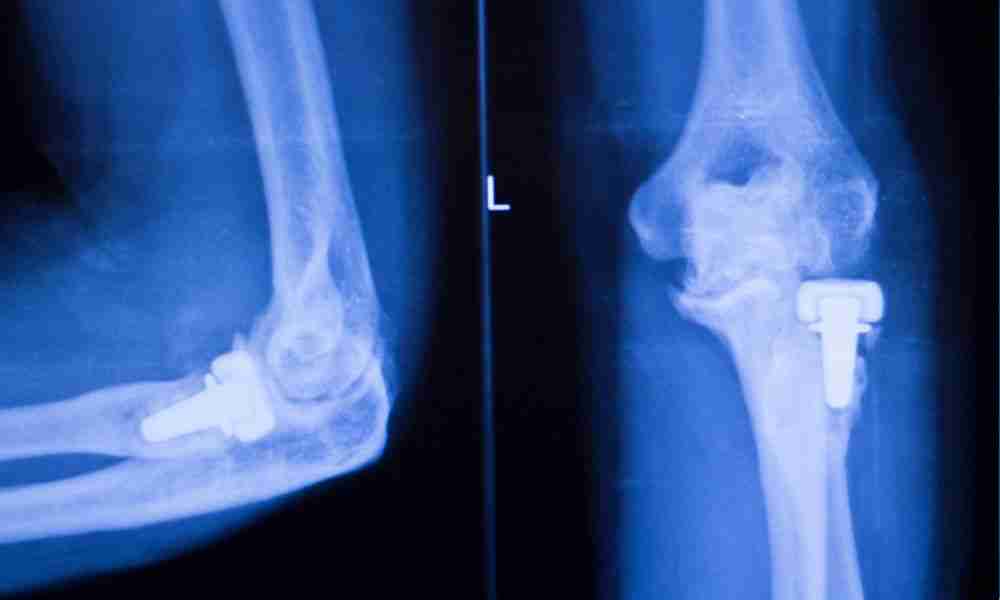

Joint replacements, such as knee, hip, and shoulder implants, have significantly enhanced the lives of individuals suffering from chronic pain and mobility limitations. However, despite their success, recalls do occur. These recalls can be concerning for patients, as they may have implications for both health and well-being. This blog will explain what a recalled joint implant means, why these implants are recalled, how patients are notified, and the steps to take if you find yourself with a recalled implant.

Design or Manufacturing Defects

A design or manufacturing process flaw can affect the implant’s function. For instance, the failure of dual-modular hip implants was attributed to issues like fretting and corrosion between components, leading to a recall (Elmallah et al., 2016).